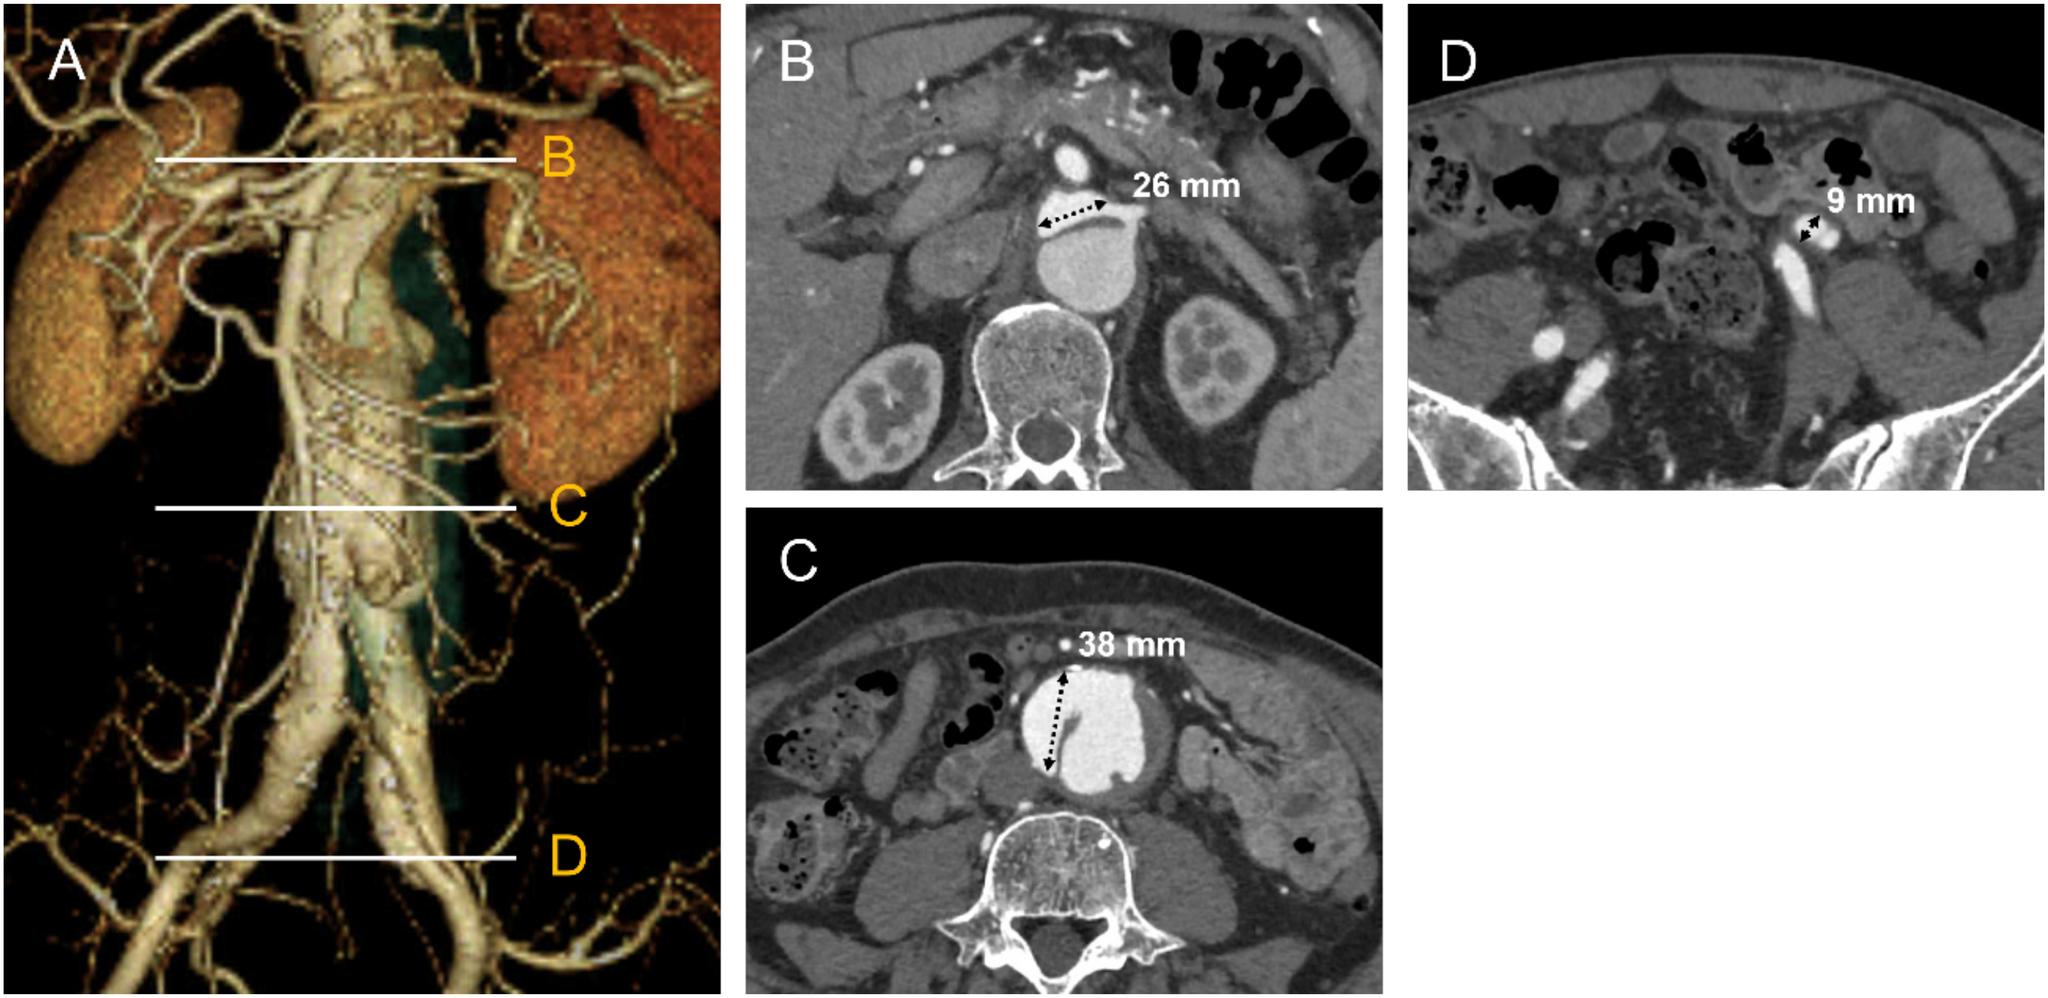

A 66-year-old man presented with an enlarging abdominal aorta false lumen, after type A aortic dissection repair. Residual entries were located at the left renal artery, abdominal aorta, and left external iliac artery. The patient underwent endovascular aortic repair with left renal artery stenting to close the entries. Completion aortography showed no false lumen flow without an endoleak, and contrast-enhanced computed tomography 1 month after the procedure demonstrated complete false lumen thrombosis. A total endovascular approach is possible for abdominal aneurysmal dilation in chronic aortic dissection when all entries can be closed using a one-stage procedure with stent grafts and/or branch stenting.

一名66岁男性在A型主动脉夹层修复术后出现腹主动脉假腔扩大。残余破口位于左肾动脉、腹主动脉和左髂外动脉。患者接受了血管腔内主动脉修复术并置入左肾动脉支架以封闭破口。术后主动脉造影显示无内漏且假腔内无血流,术后1个月的增强计算机断层扫描显示假腔完全血栓形成。当使用覆膜支架和/或分支支架通过一期手术能够封闭所有破口时,对于慢性主动脉夹层的腹主动脉瘤样扩张采用全血管腔内治疗方法是可行的。